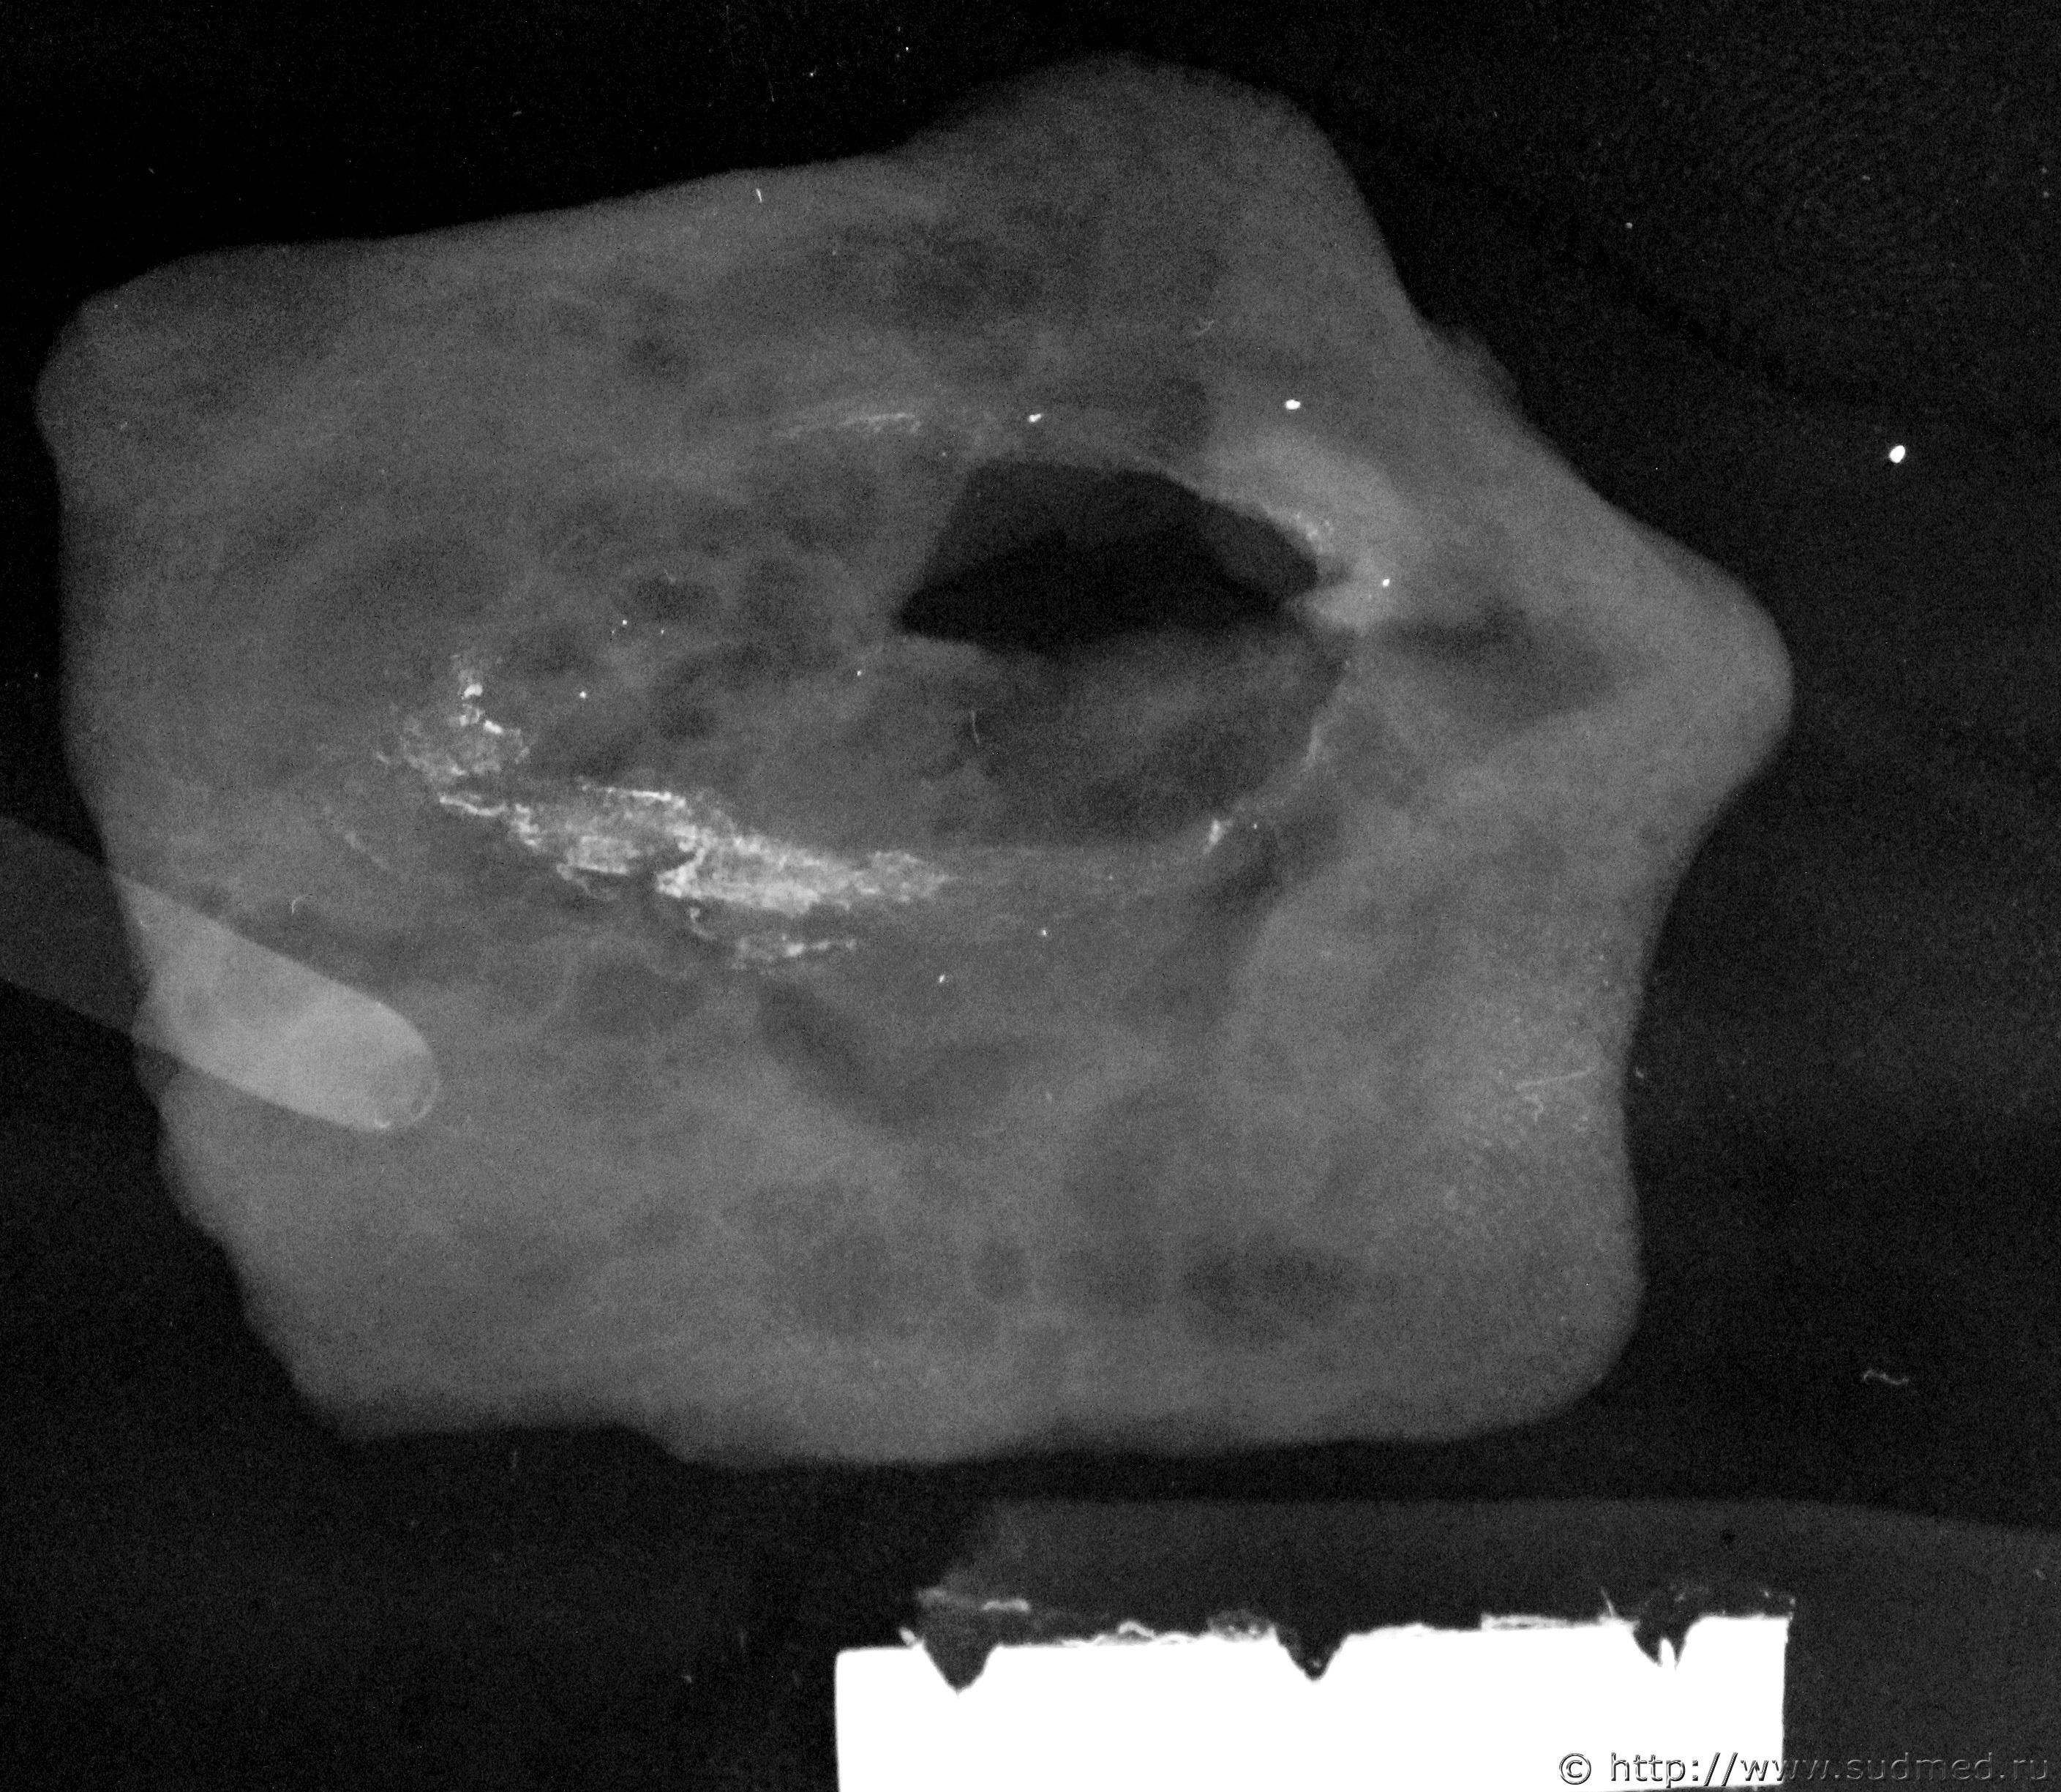

Рентгенографическое исследование препарата кожи с раной.

Непосредственно по краям просветления имеется близкой к овальной формы, более узкая, прерывистого характера плотная тень, относительно тени препарата кожи, а так же в области краев просветления соответствующих ране, имеются множественные мелкоточечные рентгено-плотные тени. Некоторые мелкоточечные тени, соответствуют расположению (локализации) частиц, похожих на металлические.

За пределами препарата тень металлической плотности? Просто загрязнение?

Какой рентгенаппарат? Такое чувство, что там папиллярный рисунок отобразился на препарате, правый нижний угол на картинке.

Просто "загрязнение" - это архивная пленка, поцарапанная скрепкой при сушки и т.д..

«РЕИС-100».

Это архив и рисунок папиллярный "наложился" после проявления.